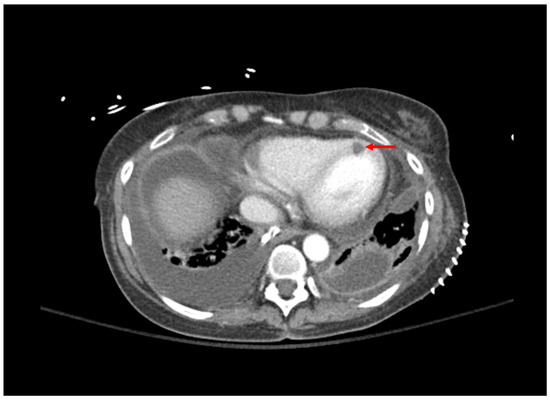

| 1: Aspergillosis | 53 YO, 5 weeks post-transplant. Received antithymocyte globulin and carfilzomib 2 weeks prior. Symptom of desaturations. | Chest CT: small right basilar empyema, partial collapse of left lower lobe, bilateral ground glass opacities, and septal thickening (Figure 1). Chest and pleural tissue culture from decortication procedure: A. fumigatus. | Voriconazole 6 mg/kg for 2 doses followed by 4 mg/kg daily. Voriconazole changed to liposomal amphotericin B after one week. Five weeks later, daily intrapleural voriconazole irrigation added for one week. | Systemic voriconazole stopped after one week for elevated hepatic function tests, intrapleural voriconazole stopped for bloody sputum. Aspergillus not redemonstrated in cultures. Patient death 4 months later due to bacterial sepsis. |